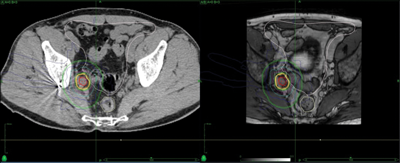

A 66-year-old man presented with a locally advanced T3b N1 prostate cancer in 2011, with an initial PSA of 33. He was treated with robotic prostatectomy and lymph node dissection followed by adjuvant prostate bed radiotherapy. Although immediate post treatment PSA levels were undetectable he had a PSA relapse in September 2012 to 2.1. Whole body MRI and Choline PET showed an apparent isolated left iliac lymph node recurrence (Figure 4). He went on to receive stereotactic radiotherapy (33Gy in 3 fractions to the lymph node - Figure 5). Follow-up imaging has shown a complete radiological response within the treated node. Eighteen months after treatment his PSA has started to rise again and most recent imaging has shown the development of a lymph node on the opposite side of the pelvis with no other sites of disease. He subsequently had further stereotactic radiotherapy to the right pelvic side wall nodes in July 2014. His PSA has dropped to 0.02 on his most recent check in January 2015.

Figure 4: Isolated pelvic lymph node recurrence on whole body MRI and Choline Pet and response to treatment.

Figure 5: Stereotactic radiotherapy plan to isolated pelvic lymph node showing marker in situ.